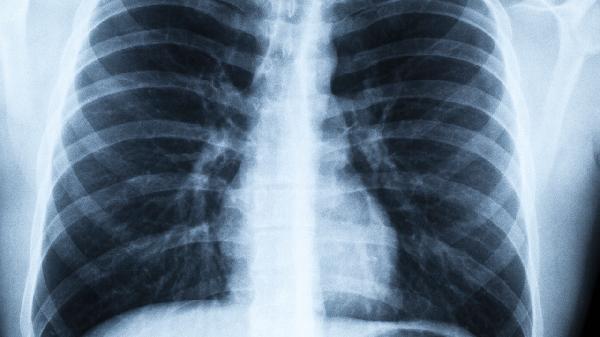

肺癌早期不是咳嗽?医生提醒:若身体出现这4大异常,千万别忽视

1、定期做低剂量螺旋CT检查,这是目前最有效的肺癌筛查手段

4、40岁以上人群建议每年做一次胸部影像学检查